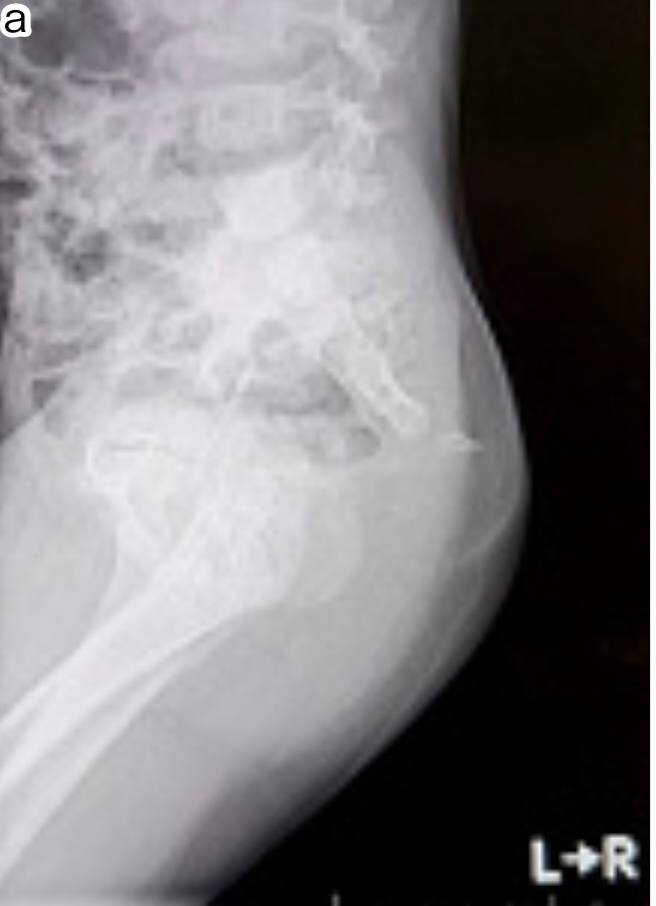

Интересная статья про пациента с хвостом. Под общей анестезией в положении лежа

на спине.

Был сделан веретенообразный разрез.

Подкожно-жировая

клетчатка была рассечена, и обнажился выступающий копчик.

Выступающие кости хвоста и покрывающий их избыток кожи были удалены. После промывания физиологическим раствором надкостницу зашили, чтобы прикрыть обнажившуюся кость, и

завершили операцию кожными швами. Материал подготовлен информационным медицинским познавательным телеграмм каналом «Искусство Пластики».